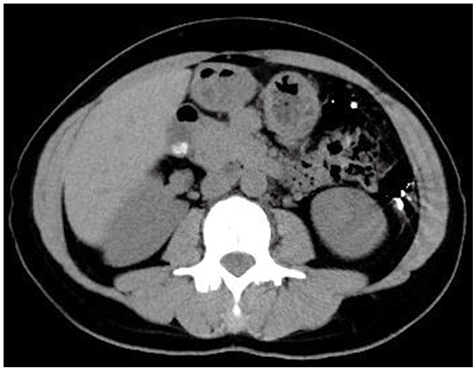

症例1

症例1の患者情報

40歳代,女性。

胆囊結石follow up目的に腹部CTを施行。

腹部症状はなし。